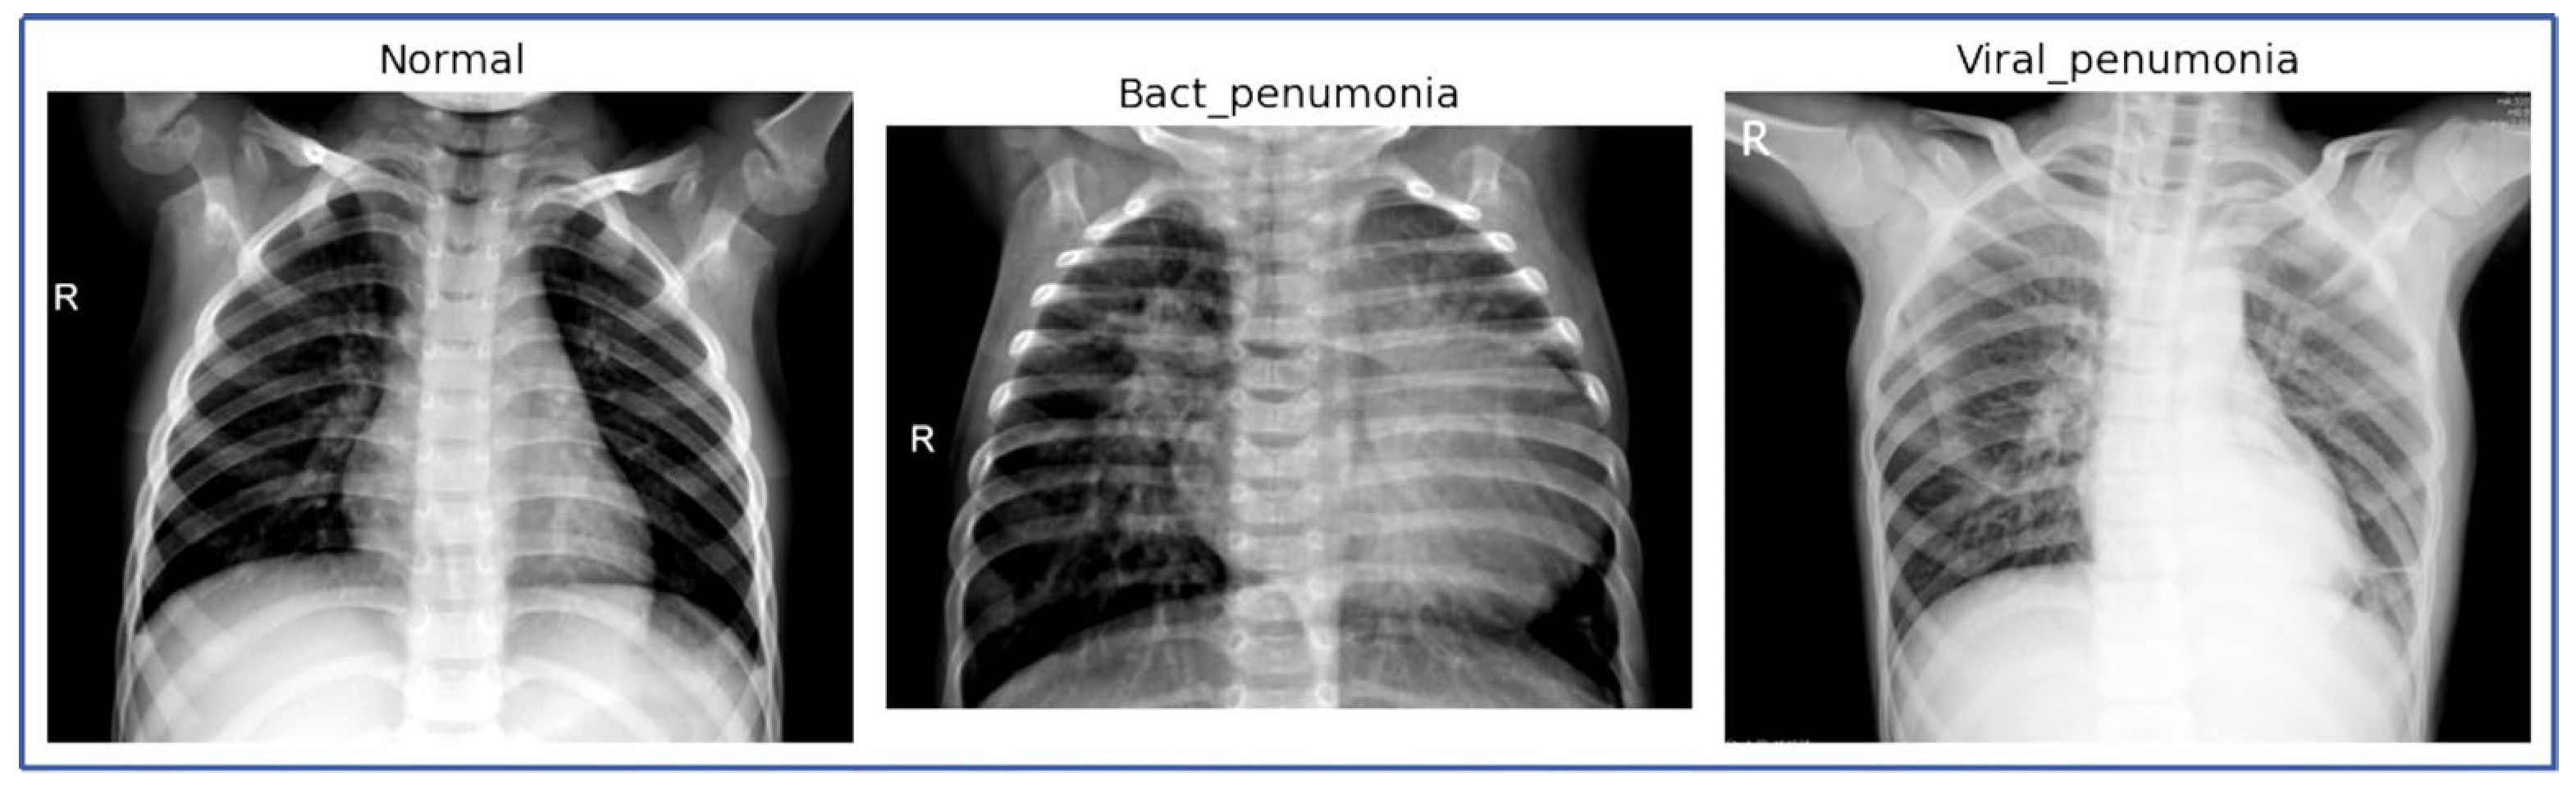

Figure 3 presents a series of CXR images categorized into three groups: NL, BP, and VP. The images reveal clear distinctions between the different conditions:

CXR images of NL, BP, and VP.

- Normal: The images labeled as ‘normal’ depict clear lung fields without any significant opacities or consolidations. The bronchial and vascular structures are visible and consistent with normal chest radiographs, which serve as a baseline comparison against the pneumonia-affected lungs.

- Bacterial Pneumonia: Several images labeled as ‘Bact_pneumonia’ exhibit prominent consolidation, with areas of opacity that suggest alveolar filling, which is characteristic of bacterial pneumonia. These radiographic findings are consistent across multiple images, highlighting the typical presentation of bacterial pneumonia.

- Viral Pneumonia: The ‘viral_pneumo’ images demonstrate more diffuse patterns, with less pronounced opacities compared to bacterial pneumonia. The images show peribronchial thickening and interstitial markings, which align with the expected radiological signs of viral infections.